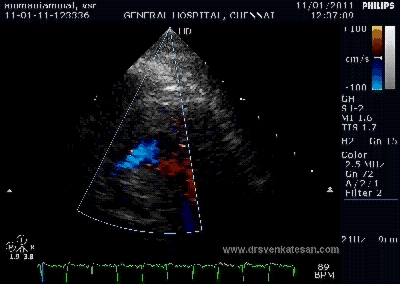

Color flow showing significant shunting from LV to RV.This shunt depends upon the LV contractile function, LVEDP and ofcourse the RV pressure

If there is severe RV dysfunction or bi ventricular dysfunction flow across the defect is inconspicuous.Brisk left to right shunting may be an indirect marker for good LV systolic function and absence of significant pulmonary hypertension.Both imply a better outcome.